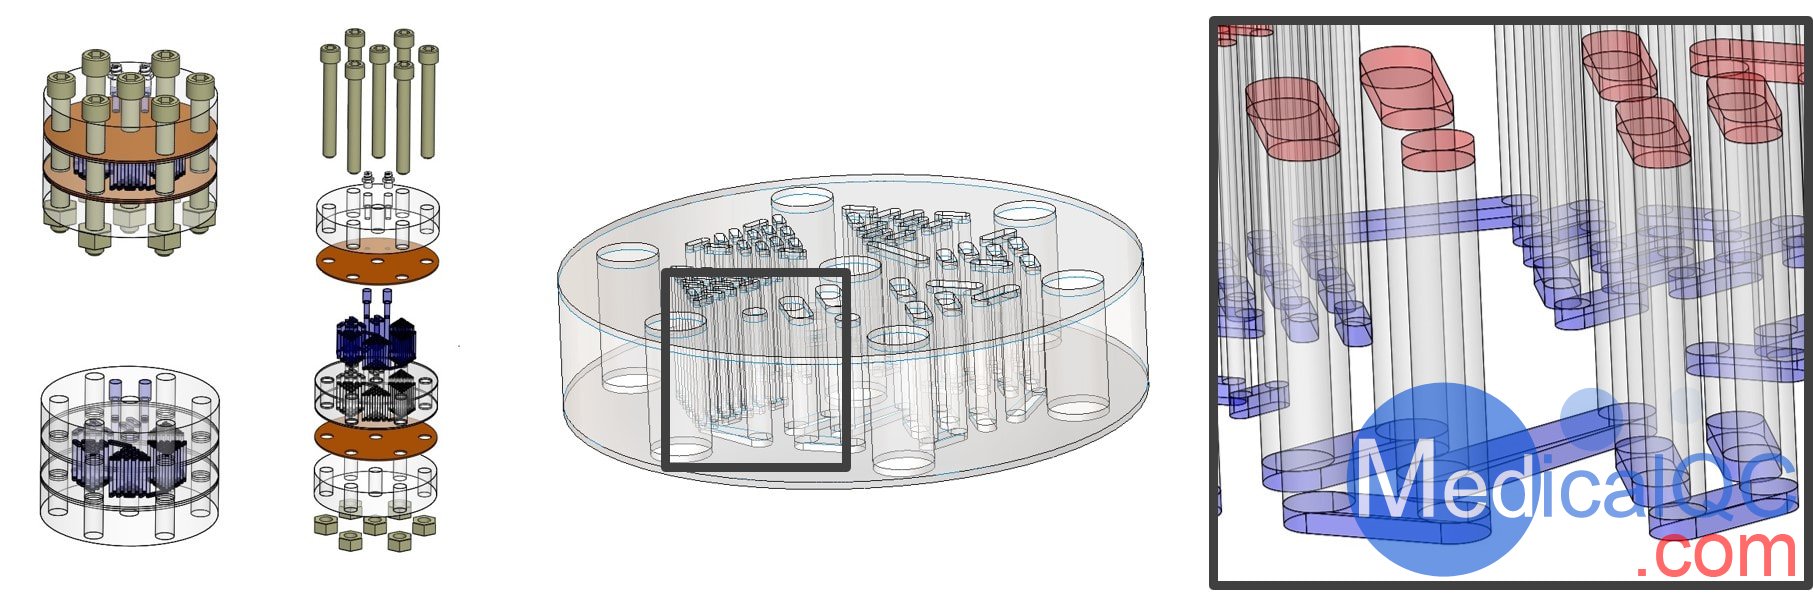

Phantech Derenzo模體是一種分辨率體模,具有不同大小的孔圖案。尺寸組中的孔的間距為2D(直徑的兩倍)。

只需確定給定的同位素和計(jì)數(shù)值即可分辨的最小孔組,即可啟用掃描儀的分辨率測試。我們的Derenzo模體具有六種不同的孔尺寸,它們圍繞模體以三角形排列。

這些體模還具有我們獲得專利的線性填充技術(shù),該技術(shù)可大大減少填充體模所需的體積,確保均勻填充并減少對體模處理者的劑量。所有這些都通過減少噪聲來改善圖像質(zhì)量。

Derenzo模體具有兩個(gè)Luer Lock配件,作為線性流體路徑的入口和出口。要填充,只需將兩個(gè)注射器連接到兩個(gè)端口即可,一個(gè)充滿活動性,另一個(gè)則是空的。當(dāng)您緩慢插入流體時(shí),您將能夠一次看到流體填充圖案桿的每個(gè)通道,從而確保均勻填充。當(dāng)流體到達(dá)空注射器時(shí),模體模式已滿。要清空模體,只需用空氣反轉(zhuǎn)該過程即可。我們的Derenzo模體有3種尺寸可供選擇:

線性填充是通過分段結(jié)構(gòu)實(shí)現(xiàn)的,該結(jié)構(gòu)創(chuàng)建了一條穿過所需體模的長蛇形通道。該鏈條既包括具有所需孔型的熱棒,也包括連接相鄰熱棒的連接通道。通過單個(gè)入口和出口,可以使用Luer Lock注射器輕松地將流體驅(qū)入體模。這樣就無需手動填充容易因表面張力而產(chǎn)生氣泡的小孔。

此外,用于創(chuàng)建復(fù)雜的孔圖案典型技術(shù)包括孔圖案的在放射性池浸沒。該技術(shù)消除了最終的輻射池,通過消除背景噪聲的主要來源,大大減少了模體的內(nèi)部體積并提高了圖像質(zhì)量。